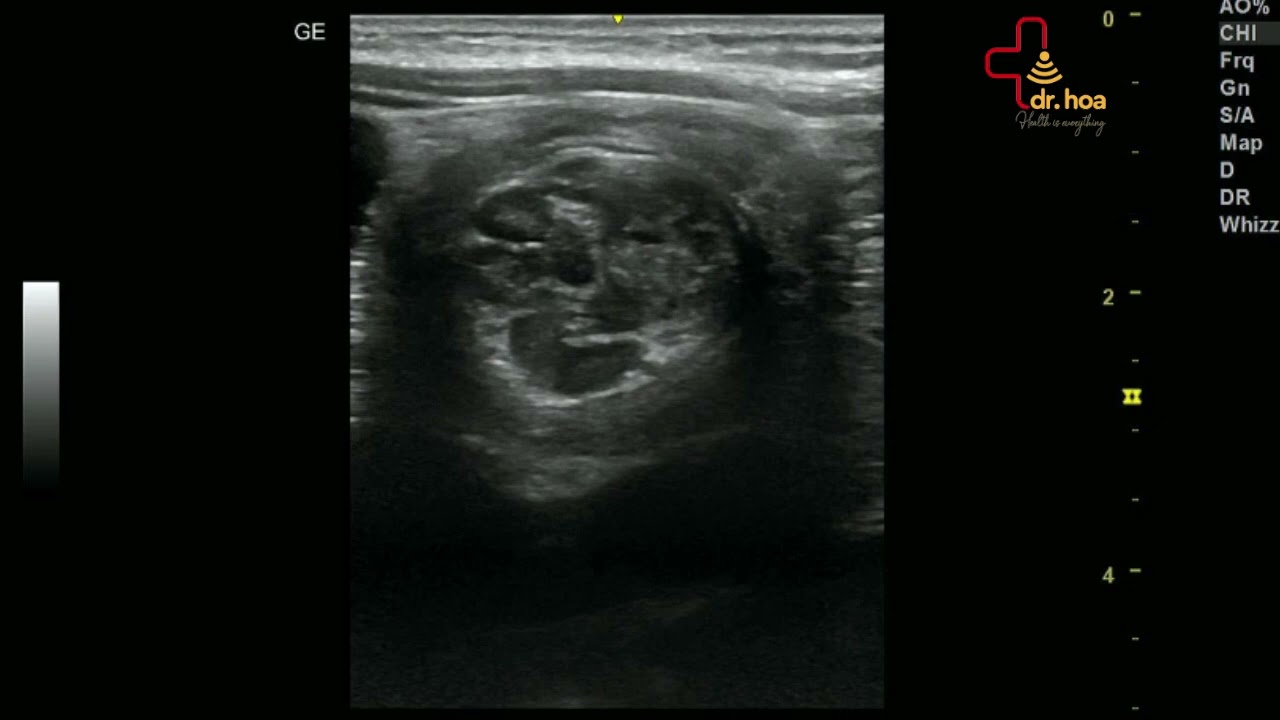

Sieu am tim hinh anh ro dep

#Siêu_âm_tim hình ảnh rõ đẹp.